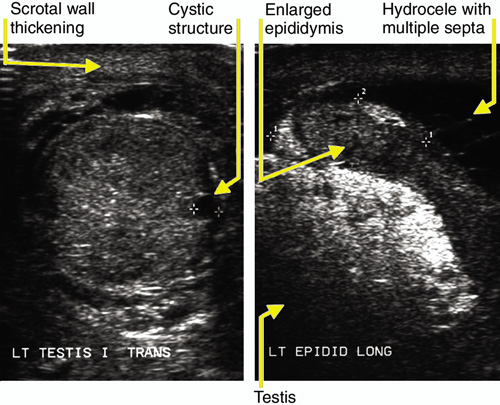

Epididymo-orchitis complicating Streptococcus pyogenes throat infection

Epididymo-orchitis can result from bacterial or viral infections. Predisposing trauma may be identified, but the majority of cases appear to be idiopathic.

In a few rare cases,1-3 streptococcal infections have been found to cause epididymo-orchitis as part of a local infection. However, all these cases occurred in preadolescent boys. There has been one report of a 17-year-old man with invasive group A streptococcal infection of the scrotum in the context of streptococcal toxic shock syndrome.4 Our case is unusual in that it occurred as a systemic illness in a 55-year-old man with haemochromatosis. This infection has not, to our knowledge, been previously described in association with haemochromatosis.5